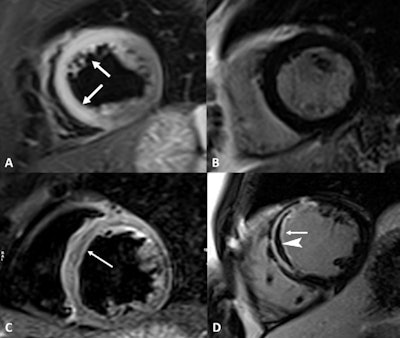

More specifically, "cine sequences ... performed on the entire short-axis, four-chamber, and long-axis planes are crucial for evaluation of ventricular function abnormalities," they added. Tissue characterization should include STIR and T2 mapping for edema, as well as T1 mapping, extracellular volume, and LGE sequences to evaluate for fibrosis and necrosis. To diagnose myocarditis, T2-based imaging and T1-based MR imaging criteria are both necessary.